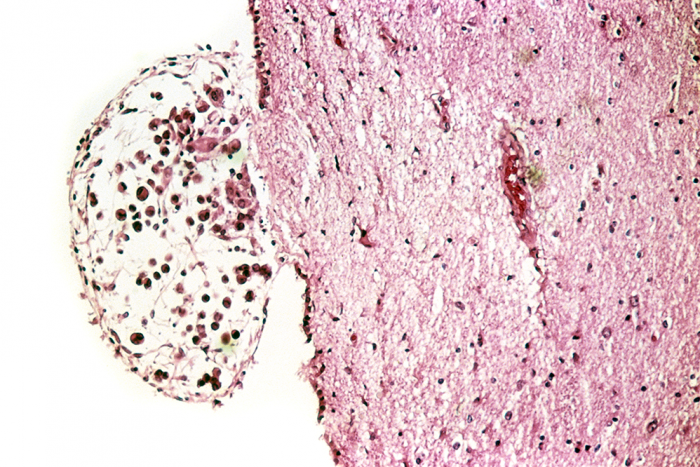

Recent research has shown that a drug known as MI-2 can kill cells that cause a fatal brain cancer. But only now have scientists been able to explain how the compound works: by targeting cholesterol production in tumors.